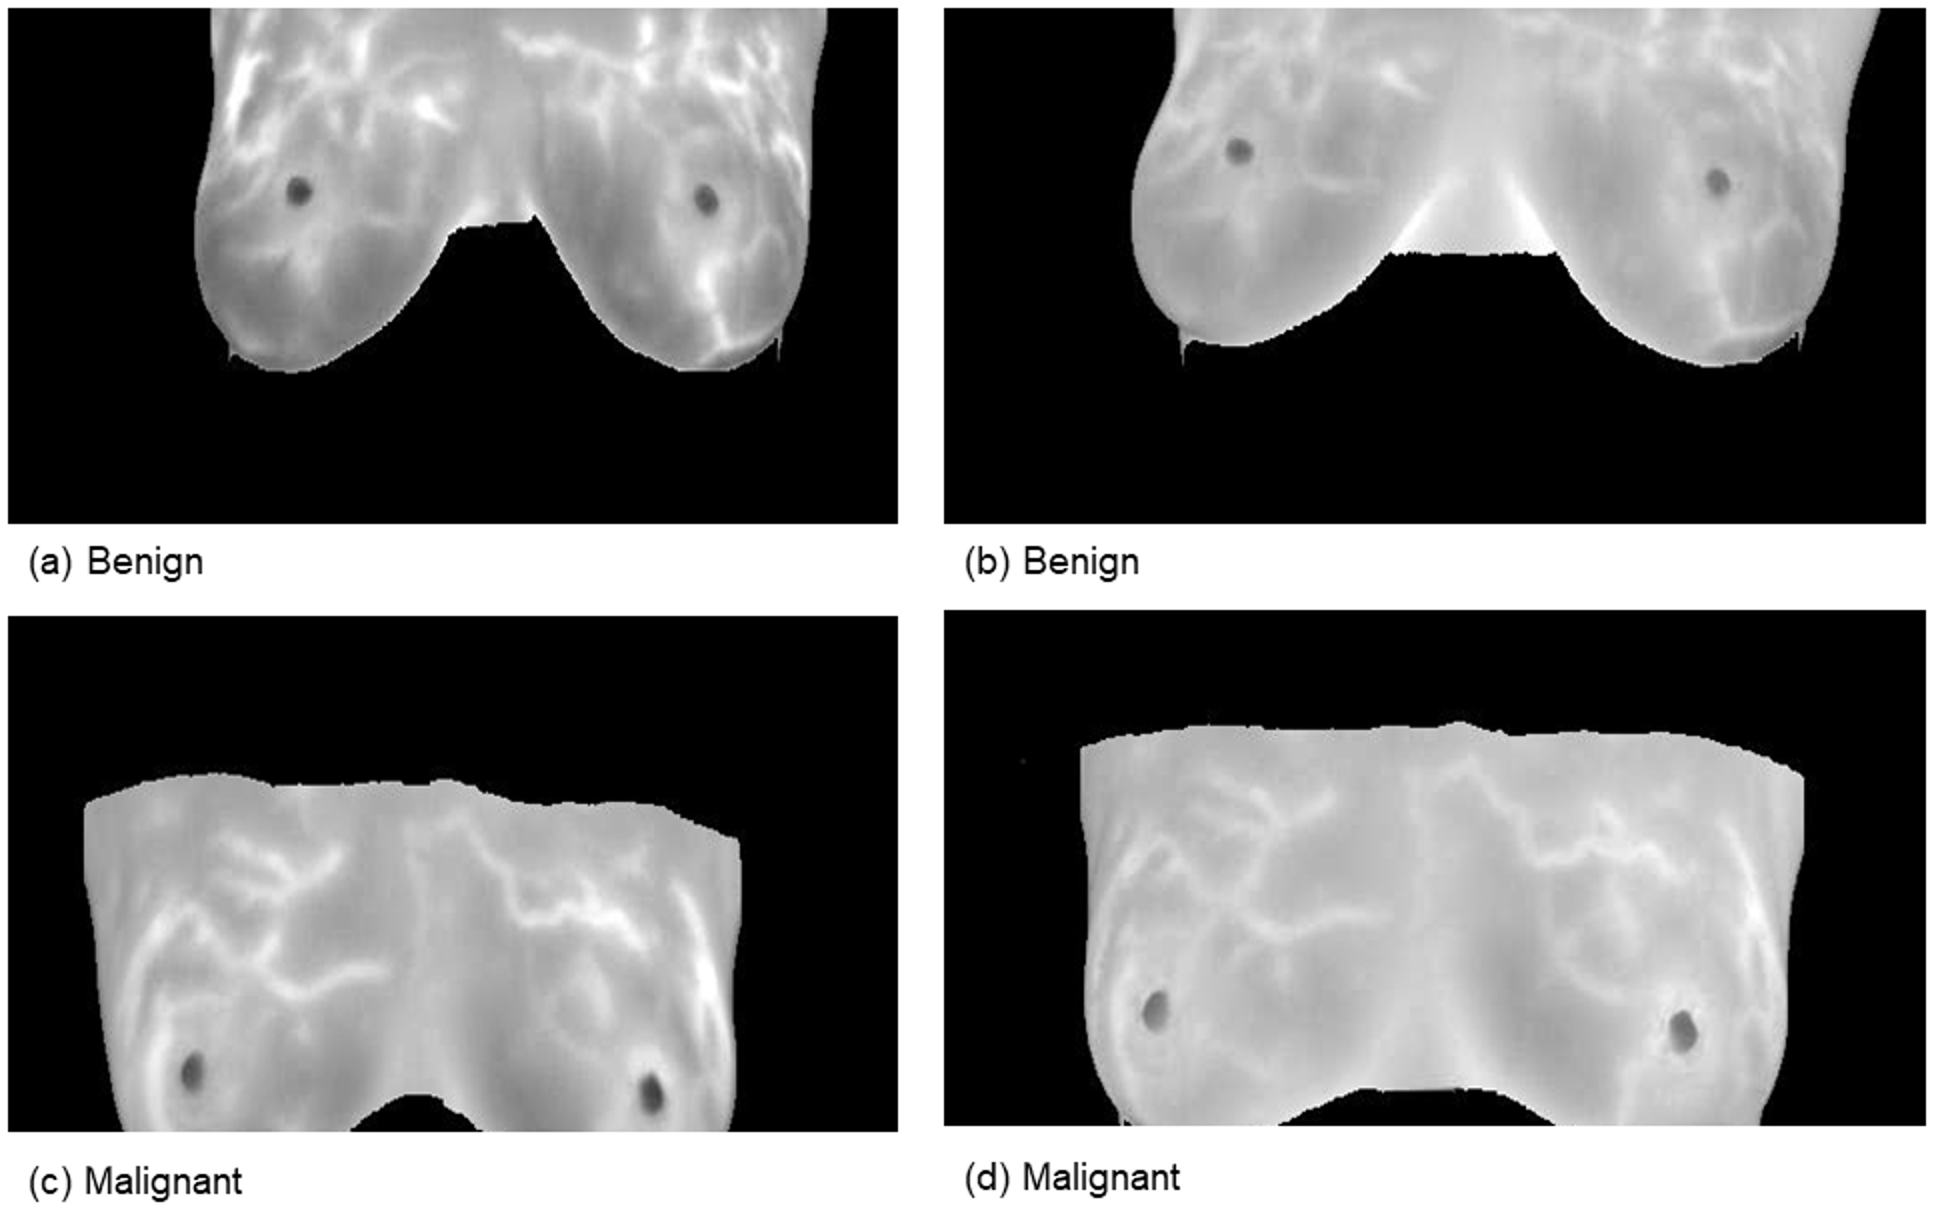

This comprehensive approach of utilizing datasets from multiple imaging modalities shown in Figure 1, Figure 2, Figure 3 and Figure 4 and summarized in Table 1, including mammography, ultrasound, MRI, and histopathological images, ensures robust model validation and enhances the system’s capacity to accurately classify benign and malignant findings. By leveraging these diverse datasets, we aim to develop a more generalizable and effective breast cancer classification system.

Figure 2. Samples from the magnetic resonance imaging (MRI) dataset.